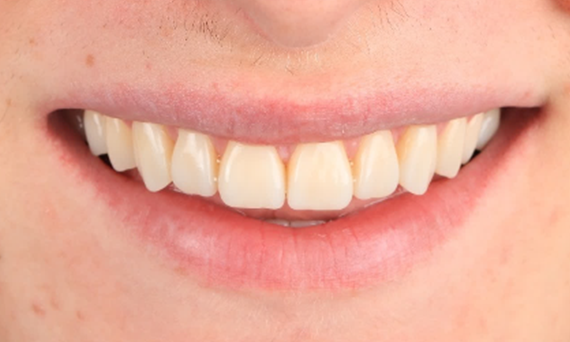

Minimal Preparation Veneers after Trauma of Upper Central Incisors

Restoration with a highly esthetic material in one day after trauma to the maxillary central incisors.

Before: Clinical Situation pre-op. Trauma of upper central incisors

After: Adhesively bonded restorations.

Dr. Mohamed Hassanien

Cairo, Egypt